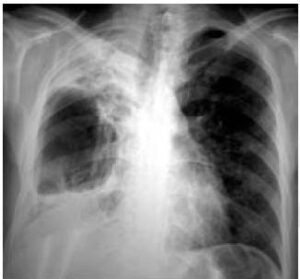

L’aspetto radiologico cambia in base al tipo di versamento pleurico:

- nel versamento libero appare un’opacità con concavità superiore (disegnando la linea di Ellis-Damoiseau), espansione dell’emitorace e spostamento del mediastino verso il lato sano a seconda della quantità di versamento.

Nel versamento pleurico massivo, se il liquido si accumula sempre di più, si ha un collasso progressivo del parenchima polmonare sottostante che può rendere completamente opaco un emitorace che apparirà completamente bianco.

I segni che ci portano verso la diagnosi sono l’opacità totale di un emitorace, lo spostamento del mediastino verso il lato controlaterale, l’abbassamento del diaframma che può assumere una forma invertita, l’allargamento degli spazi intercostali e assenza di broncogramma aereo (in quanto vi è un aumento di densità, non si vedrà il broncogramma aereo).